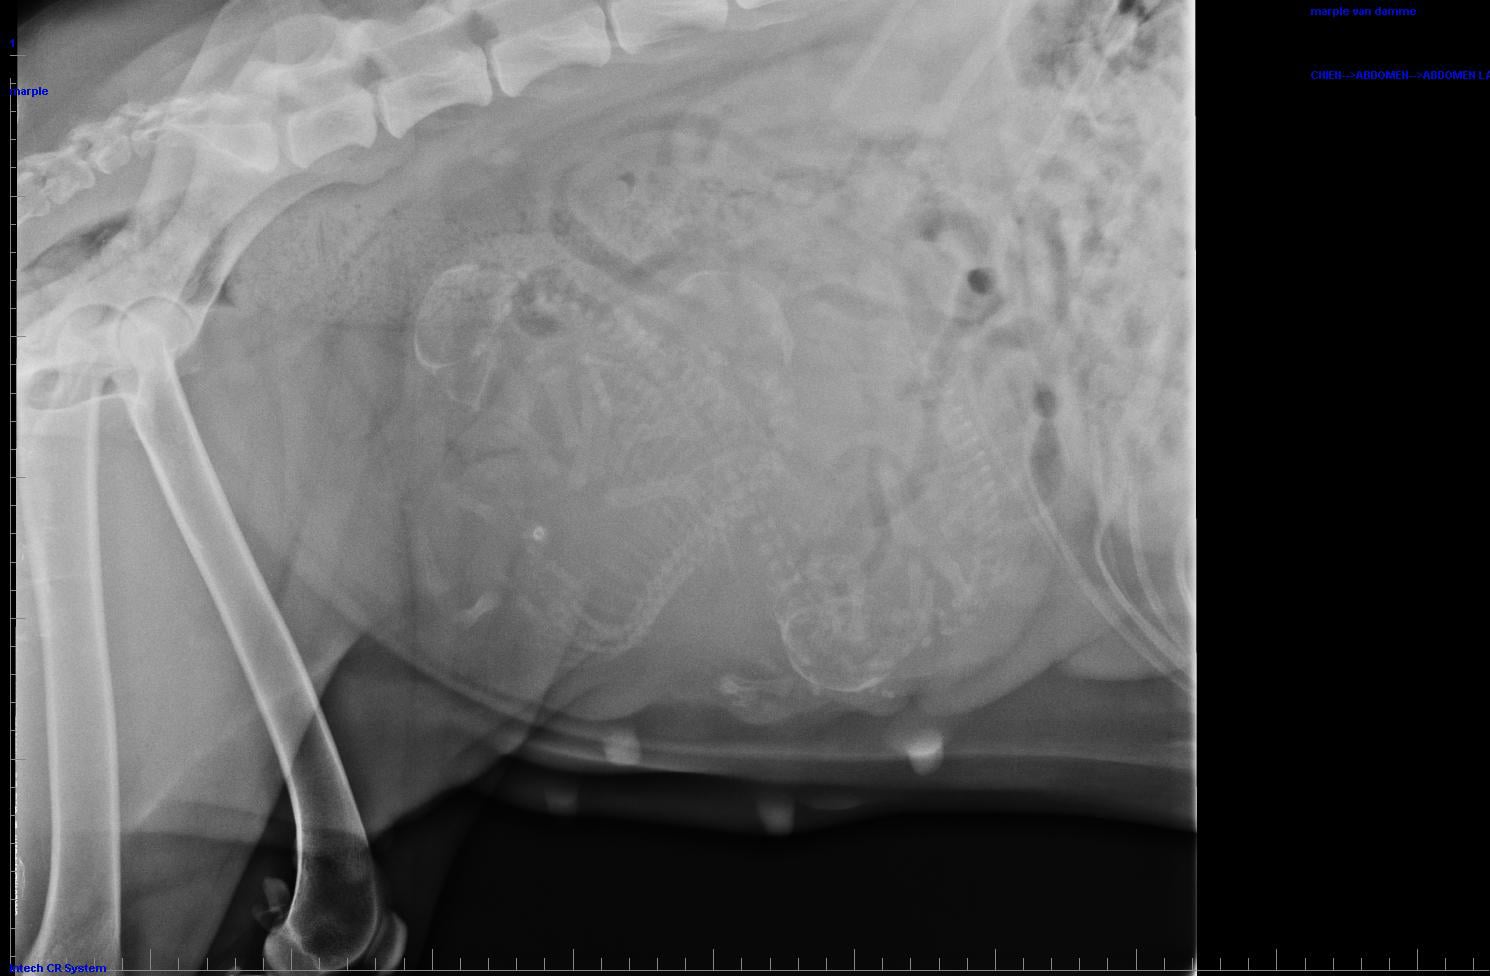

Miss Marple is vandaag 58 dagen zwanger.

We verwachten 3 mooie pups, het mochten er iets meer zijn geweest maar toch zijn we heel gelukkig.

Nu is het afwachten naar de bevalling

Vandaag 60 dagen ver. Miss Marple heeft het lastig door de warmte Vanaf nu kunnen en mogen de pups geboren worden. We zijn er klaar voor !